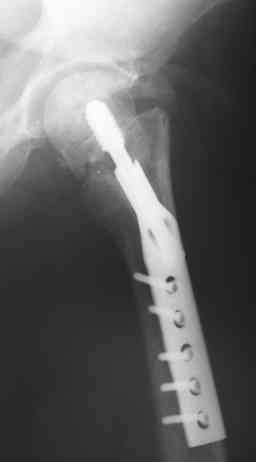

Пациентка 39 лет в декабре 2007г. в результате ДТП получила

оскольчатый метафизарный, Т-образный полный перелом мыщелков правого

бедра, базальный перелом шейки левого бедра. Перелом правого бедра лечили

аппаратом Илизарова, перелом шейки левого бедра синтезировали DHS.

Имя     : январь 2008.jpg

Тип     : image/jpeg

Размер  : 14928 байтов

Описание: отсутствует

Url     : http://weborto.net:8080/pipermail/ortho/attachments/20081116/4693b436/attachment-0006.jpg